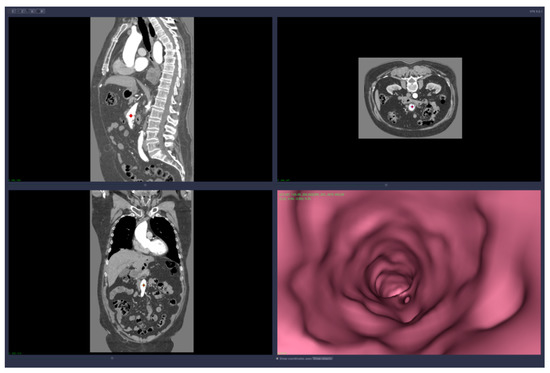

• 3D reconstruction and visualization of arteries (see Figure 1 and Figure 2)

Figure 1. Images of the 3D CT reconstruction and 2D sections.